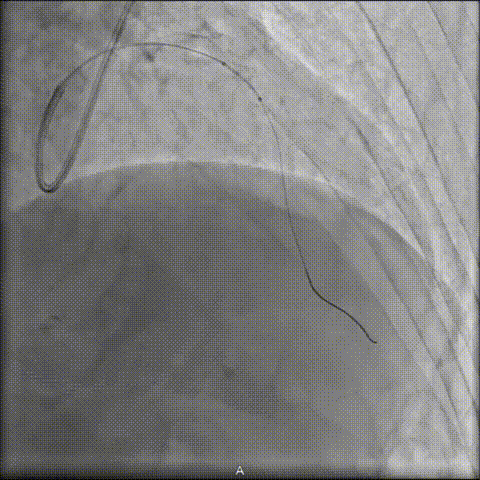

4 前向冲击波导管成功”开路”

经充分评估病情后,陆浩教授将前向冲击波导管作为关键突破策略:导管推送并稳抵病变后,实施“推进式治疗”,经6周期治疗后,术者即感明确的“突破感”,导管随之成功通过钙化病变段。

后续NC球囊扩张充分,支架植入顺利。